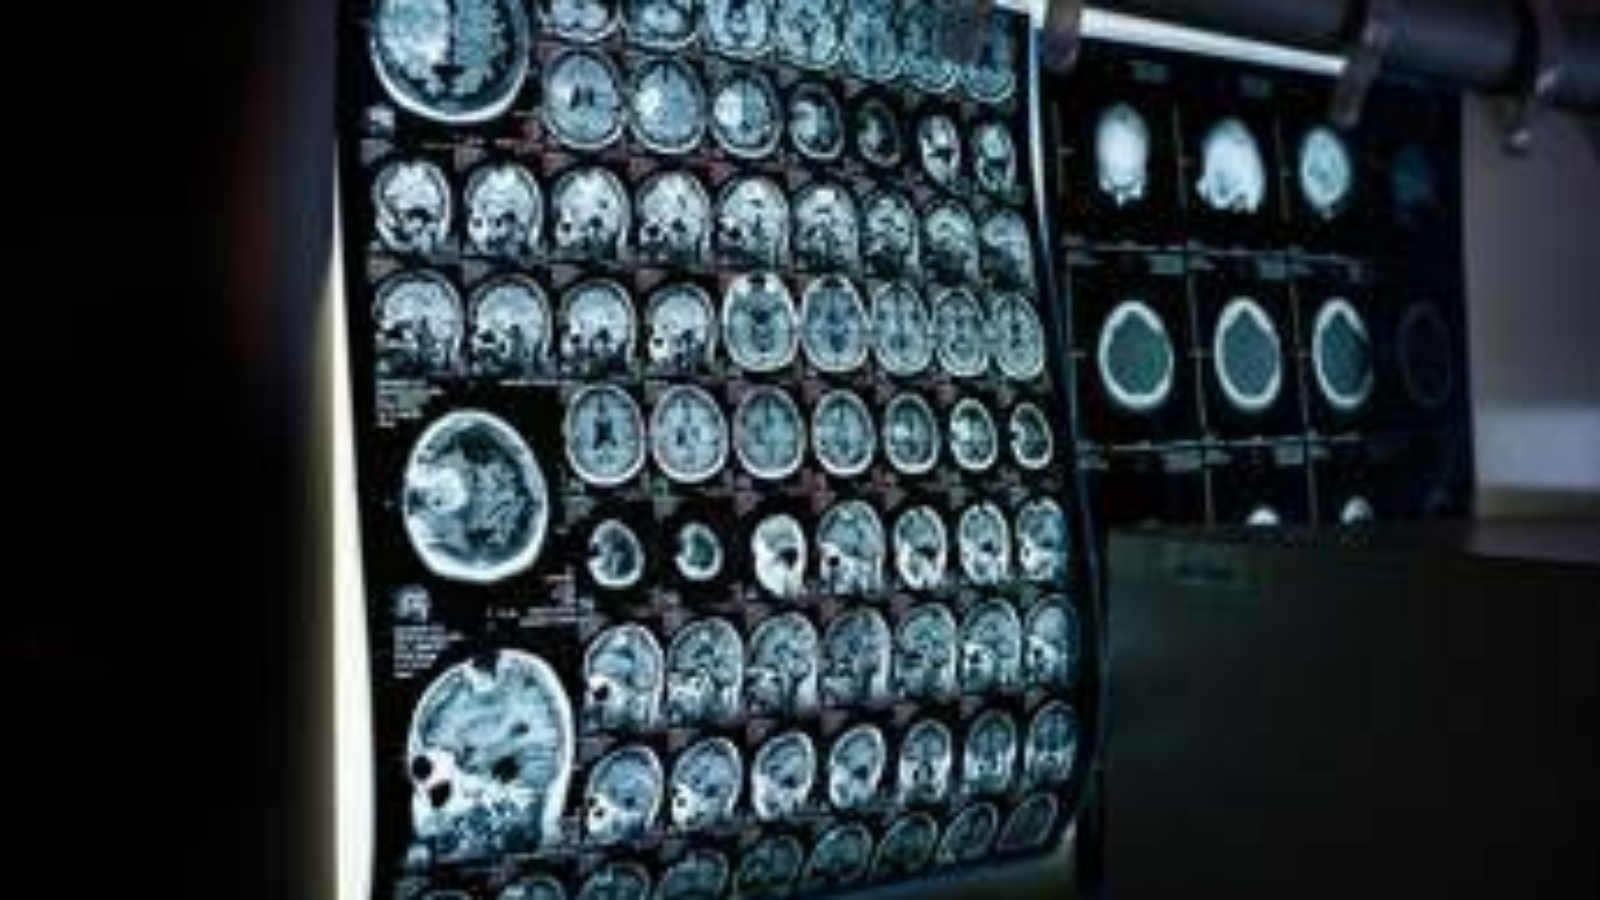

Uno spray nasale ferma l'invecchiamento del cervello, lo studio

(Adnkronos) – E’ stato testato su modelli animali in 2 dosi: ha dimostrato di migliorare la memoria e dissipare la ‘nebbia mentale’ in poche settimane